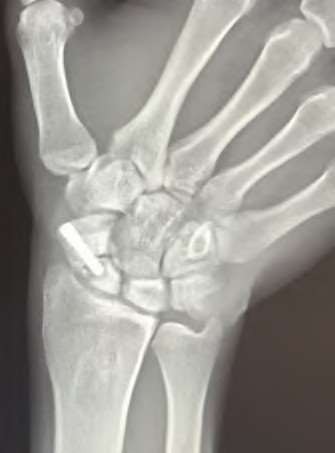

A 20-year-old park ranger trips and falls onto his right wrist with the wrist in extension and pronation. The local urgent care orders both radiographs and a CT, which you review and determine to be normal. The patient complains of ulnar-sided wrist pain. On exam, his tenderness is localized to the fovea. Ulnar deviation also causes him pain. There is no snapping sensation with wrist supination, flexion, and ulnar deviation. He otherwise has 5/5 strength to his first dorsal interosseous muscle with 4mm static two-point discrimination on the ulnar side of the 4th digit. Which of the following injuries is most likely responsible for his symptoms and exam?